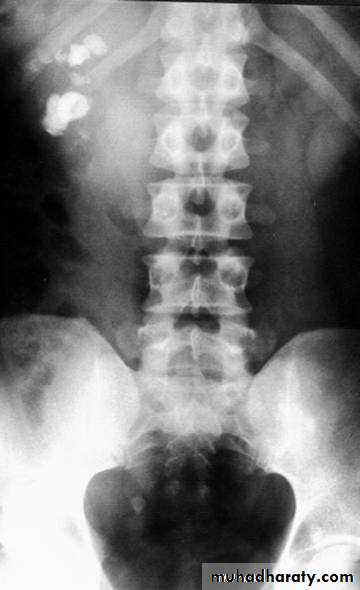

2-Blood urea & serum criatinin 3-radiological:- KUB (kidney,ureter,bladder):-A-BonesSB-Soft tissueC-StonesA plain radiograph of the abdomen and pelvis includes the area above both adrenal glands and extends to 2 cm below the symphysis pubis

KUB: site, skin, sex, stones, psoas shadow, skeleton, and soft tissue shadow